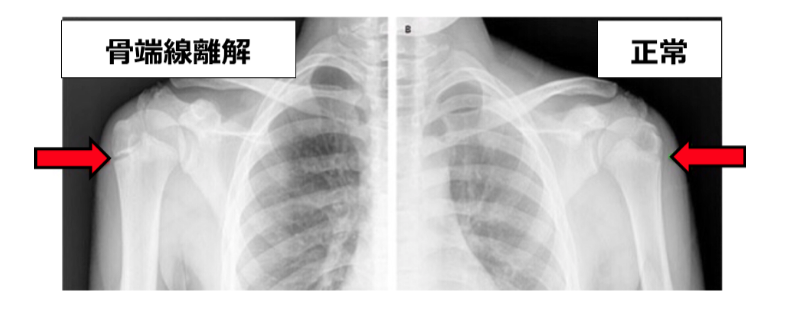

上腕骨骨端線障害(リトルリーグショルダー)

画像引用元:リトルリーガーズショルダー – り整形外科クリニック

成長期の子どもに見られる障害で、上腕骨の骨端線に負担がかかることで痛みが出るとされます。

投球数の多い小中学生に多く、安静が指示されることが一般的です。